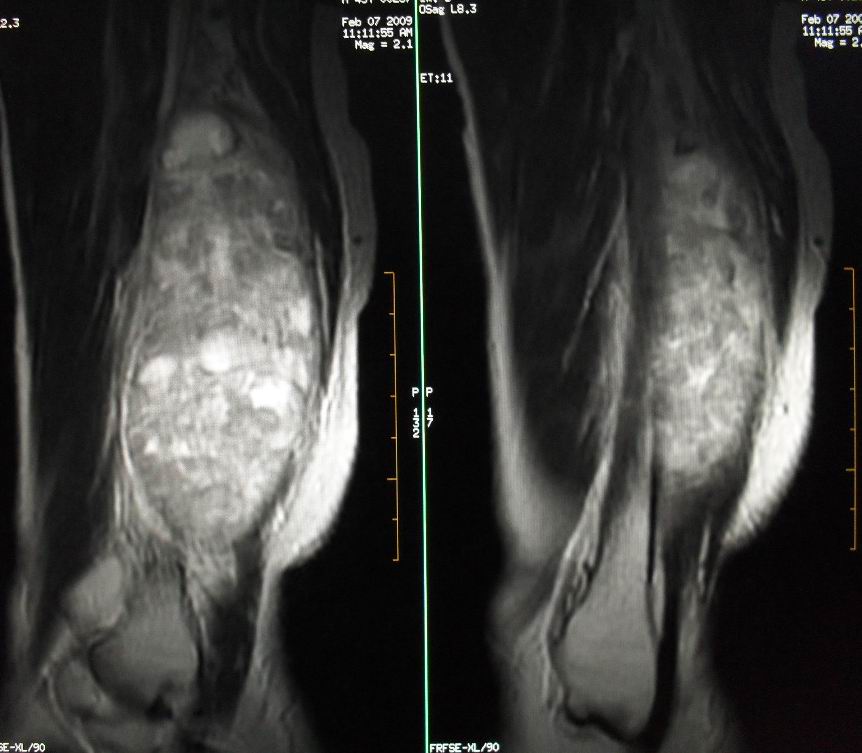

患者男43,右小腿后部软组织肿块2~3年,近期增大明显。平扫加强化。已手术。

1)呈等长t1混杂t2信号,其内见多发类圆形长t1长t2异常信号,病灶主要沿肌间隙生长,但有完整的包膜.gd_dtpa显示:病灶呈明显不均匀的强化,但未见迂曲的强化血管影.

本病例软组织肿块大,内信号不均匀,有多个囊变区,包膜完整,本片经山东省医学影像研究所mri室王主任会诊术前考虑良性肿瘤,不排除恶变,在北京某医院手术,穿刺及术后病理均为良性,未发现恶变。

本病例软组织肿块大,内信号不均匀,有多个囊变区,包膜完整,本片经山东省医学影像研究所mri室王主任会诊术前考虑良性肿瘤,不排除恶变,在北京某医院手术,穿刺及术后病理均为良性神经鞘瘤,未发现恶变。[face=宋体][/face]

谢谢楼主反馈手术结果!该病灶巨大,但与周围组织分界清晰,其内低密度规整,均支持良性病变。